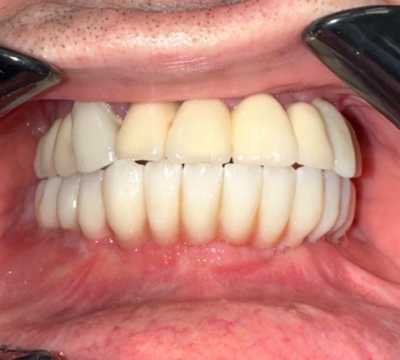

Pacientul Nicu D., în vârstă de 50 de ani, s-a prezentat în cabinet cu o edentație totală mandibulară în urma unei boli parodontale.

Împreună cu pacientul am hotărât realizarea unei lucrări protetice fixe inșurubabile pe 6 implanturi (implanturi Paltop). Lucrarea a fost realizată din ceramică pe zirconiu.

Implantul Paltop oferă posibilitatea realizării unor lucrări cu o estetică impecabilă și o afectare minimă a țesuturilor la locul implantării. Profilul concav al bontului protetic ajută la formarea unui țesut gingival dens la nivelul legăturii transgingivale scăzând vizibilitatea bontului.